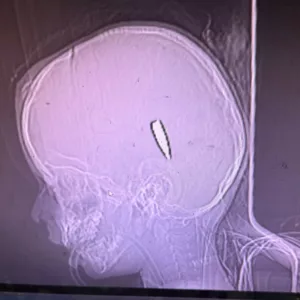

قدمت لنا الدكتورة ميمي سيد، التي عملت في خان يونس من 8 آب/ أغسطس إلى 5 أيلول/ سبتمبر، هذه الصور بالأشعة السينية. وقالت: “جاءني العديد من الأطفال، معظمهم تحت سن 12 سنة، أصيبوا برصاصات في الرأس أو الجانب الأيسر من الصدر، وعادة ما كانت الإصابة برصاصة واحدة، وكان المرضى يأتون إما وقد فارقوا الحياة، أو في حالة حرجة ويموتون بعد وقت قصير من وصولهم”.